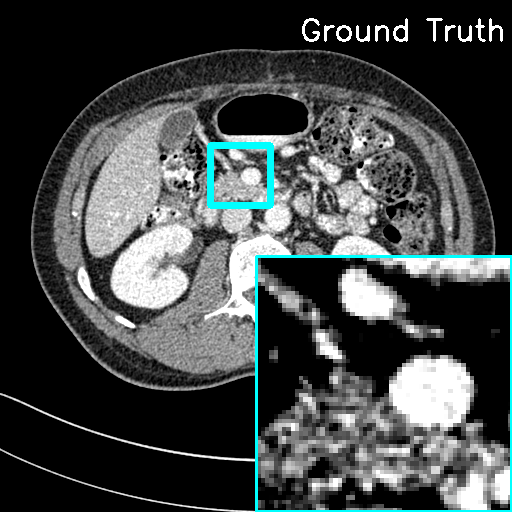

We then evaluate the ‘plug-and-play’ capability of LInFBP by integrating it into recent state-of-the-art CT reconstruction methods, including iRadonMap [10] and DICDNet [34]. Specifically, we replace the sinusoidal backprojection layer in iRadonMap with our continuous backprojection (LInFBP) to form iRadonMap+F-LInFBP and iRadonMap+L-LInFBP. Similarly, we replace the traditional FBP module of DICDNet with LInFBP. Fig. 7 shows the radar charts which display the quantitative measurements on selective reconstructed images at 100 views (first row) and 146 views (second row) from iRadonMap, iRadonMap+F-LInFBP, iRadonMap+L-LInFBP, DICDNet, DICDNet+F-FBP and DICDNet+L-FBP, respectively. It is evident that the proposed LInFBP consistently enhances the reconstruction performance of each model it is combined with. This improvement can be attributed to the effective enhancement of the accuracy of the radon transform by the proposed LInFBP, enabling it to be seamlessly integrated into existing reconstruction methods to readily enhance their reconstruction performance. Fig. 8 shows the reconstructed images and error maps obtained using different methods. When combined with the proposed LInFBP, iRadonMap and DICDNet demonstrate superior performance compared to their counterparts without being equipped with LInFBP, exhibiting fewer noise-induced artifacts and reduced residual errors in the error maps, as observed in the zoomed-in ROI images indicated by the cyan box.

Moreover, Fig. 9 depicts the MTF curves of different methods, which refers to an image’s ability to preserve contrast as resolution increases, in the ROI indicated by the red circle. It can be seen that the state-of-the-art approaches achieve an improvement when being integrated with our method. This improvement can be attributed to the design of the original iRadonMAP and DICDNet, which leverage multi-layer neural networks with robust denoising capabilities to ensure high-quality output with perhaps some degree of contrast smoothing. On the contrary, our method mitigates the interpolation errors in the backprojection process of these models, allowing for better preservation of image details. Consequently, our approach retains contrast more effectively, leading to higher MTF curves and overall improved performance. Specifically, the MTF curves of DICDNet+F-LInFBP and DICDNet+L-LInFBP overlap, indicating that F-LInFBP and L-LInFBP achieve similar contrast preservation in the images. These results demonstrate the effective ‘plug-and-play’ capability of the proposed LInFBP.